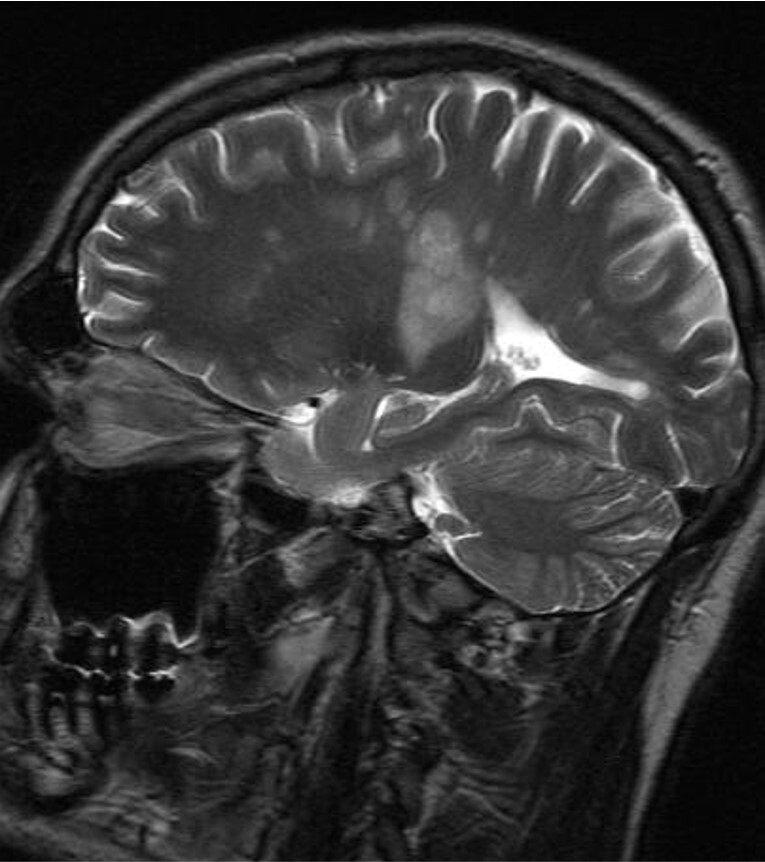

Демиелинизирующие заболевания мозга: МРТ изображения